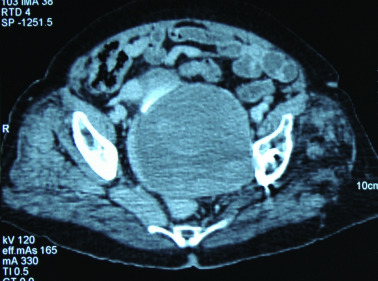

In direct radiographs (Fig. 3 ), the femoral head was located eccentrically and superiorly within the acetabular cup, indicating a severe polyethylene wear. A lytic area larger than 1.5 cm was present in the ischium and also in the superior pubic ramus. Radiographic tear drop was not visible. The acetabular socket was adjacent to the Köhlers line. Despite these severe lytic changes in the inferior acetabulum and ischion, the superior acetabular coverage was almost intact, with a bone defect less than 2 cm. The acetabular defect was classified as grade 2C according to Paprosky classification.1

AP radiograph. Loosening and osteolysis around the acetabular component, loss of ...

AP radiograph. Loosening and osteolysis around the acetabular component, loss of the tear drop and proximity of the acetabular component to the Köhlers line.